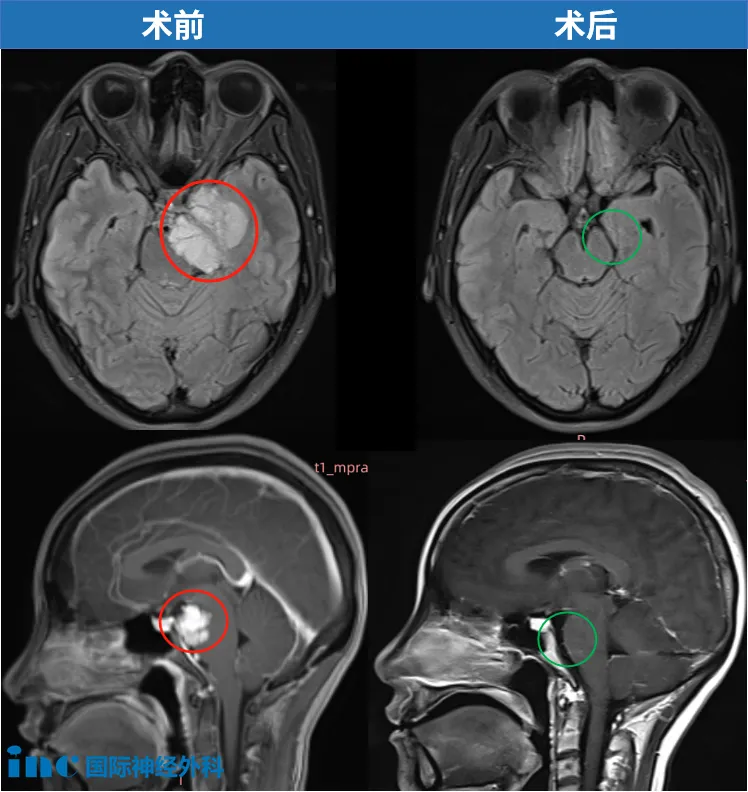

41岁的周女士同样在体检中发现桥小脑角(CPA)区脑膜瘤。肿瘤虽小,位置却极其棘手:与纤细的滑车神经、三叉神经紧紧粘连,同时还压迫桥脑和中脑——这是生命的中枢。她没有等到剧烈头痛或面瘫偏瘫出现,正是这份体检报告,让她在神经功能尚完好时抓住了治疗的“黄金窗口期”,最终由巴教授主刀完成高难度手术,及早解除风险。